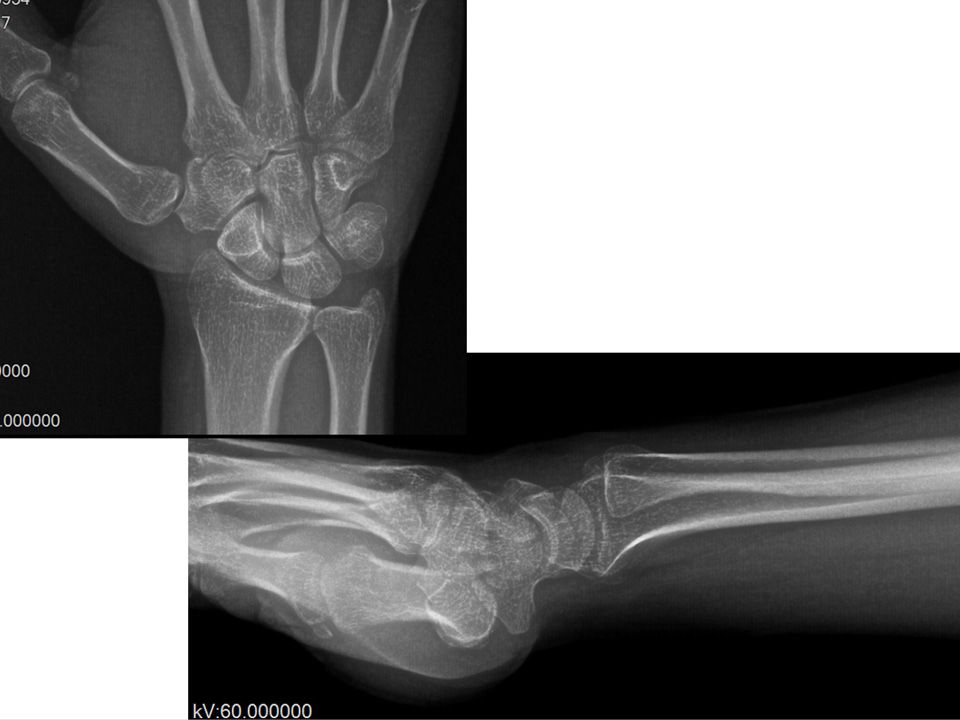

Case 07 - Occult Ganglion+Scapholunate Ligament Injury+Dorsal Capsular Dissociation 25 yr, male, , right hand dominancyHe had right wrist pain located dorsaly due to fall 2,5 years agoNo pain relief after NSAIDs, rehabilitation and splintingWatson shift test +, finger extension test +